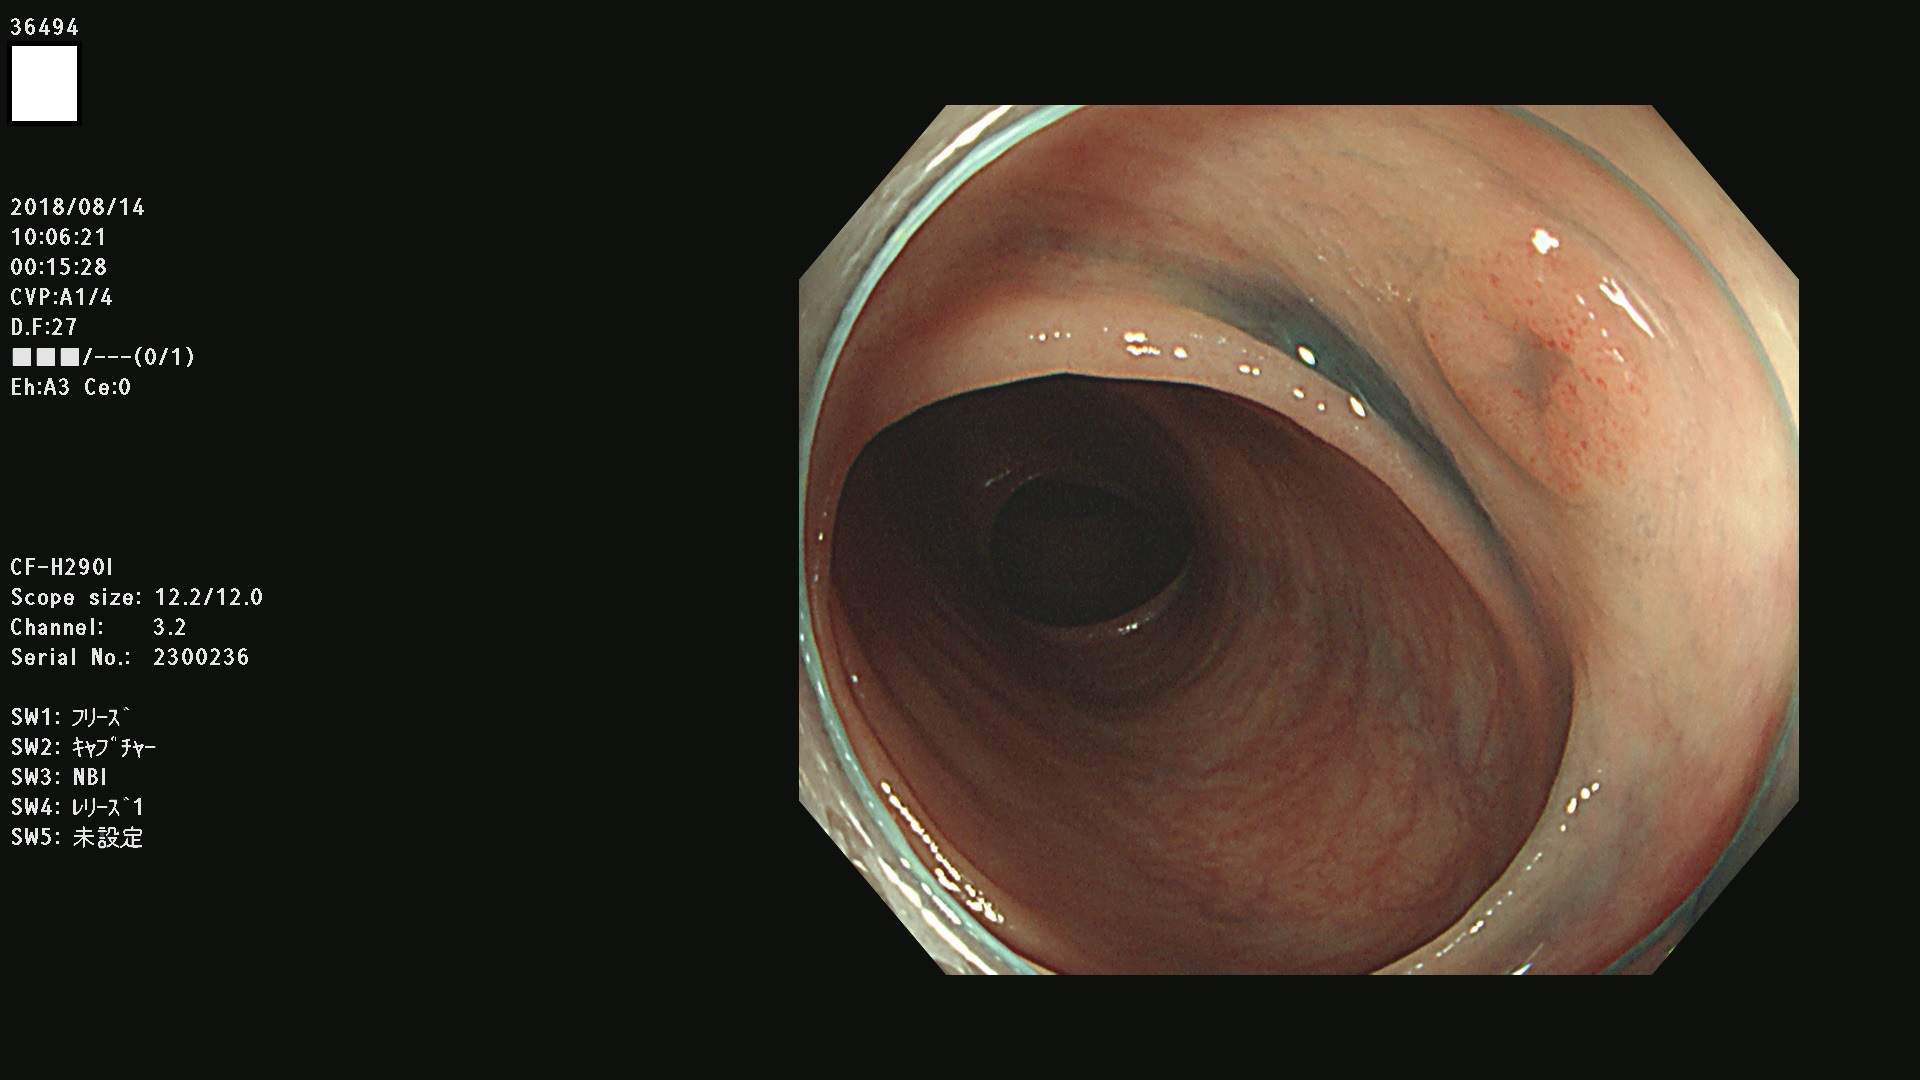

36400(SSAPのみ) 36402 36403 36404 36405 36406 36407 36408(SSAPのみ) 36412 36413 36414 36415 36416 36417 36418 36420 36422 36423 36424 36425 36426 36428 36429 36430 36431 36434 36435 36436 36437 36438 36440 36443 36447 36448 36449 36450 36452 36454 36458 36459 36460 36462(SSAPのみ) 36463 36464 36465 36466 36470 36471 36472 36473 36474 36475 36476 36478 36480 36481 36482 36484 36487 36488 36489 36490 36492 36494 36495 36496 36497 36498

発見困難で危険性の高い平坦型病変(上記100名より抽出)